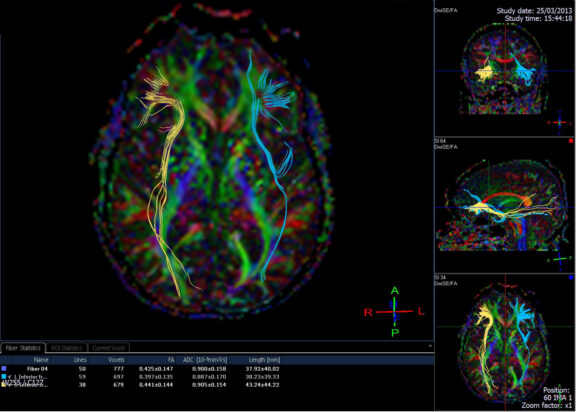

Inside the Dyslexic Brain: